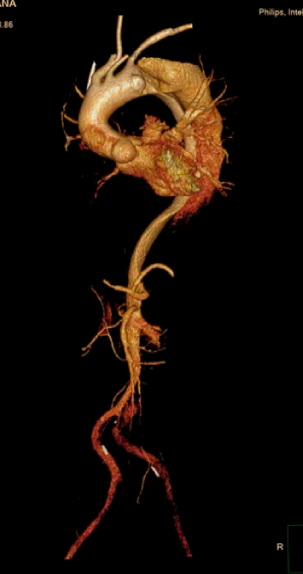

Chest X-ray showed total opacification of the left hemithorax with mediastinal shift. Non-contrast CT revealed a massive pleural collection obscuring the aortic contour, suggesting hematothorax. After stabilization and VATS decompression, CT angiography demonstrated a DeBakey type III (Stanford B) dissection from the arch to the left iliac artery with aneurysmal dilation and impending rupture distal to the left subclavian artery.

Aortography revealed a descending thoracic aortic dissection with an entry tear just distal to the left subclavian artery. Through right femoral access, a SEAL thoracic stent graft (38¡¿150 mm) was deployed across the rupture site. A Bentley BeGraft chimney stent (10¡¿57 mm) was placed via left brachial access to preserve subclavian perfusion. Final angiography confirmed proper stent apposition and complete exclusion of the rupture without endoleak.